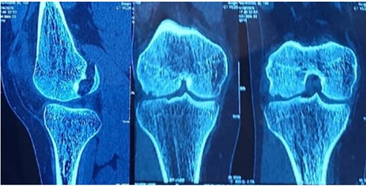

The patient was administered painkillers and ice fomentation and underwent an X-ray of his knee joint. An osteochondral fragment was visible in the knee joint, but we were not able to determine where the origin of the fragment was. A computed tomography scan of the knee joint was performed, and the fragment was identified to be originating from the distal LFC and was measuring 2.5 cm × 2.5 cm. The Insall Salvati ratio was 1.36, and the Caton Deschamps Ratio was 1.6. The Tibial Tuberosity–Trocheal Groove (TT–TG) distance was 20 mm, and his knee was a Dejour type B. A standing scannogram was not possible for the patient due to pain. The decision to avoid a tuberosity osteotomy was made as the TT-TG distance was just at the borderline with a slightly high Caton–Deschamps index. The decision to perform a lateral parapatellar arthrotomy with a strong medial patellofemoral ligament (MPFL) reconstruction was deemed sufficient to maintain patella stability. The final decision would be taken intraoperatively after tightening of the MPFL graft regarding the requirement of a tuberosity osteotomy. Fig. 2, 3.

Figure 3: Computed tomography scan of right knee – coronal and sagittal cuts.